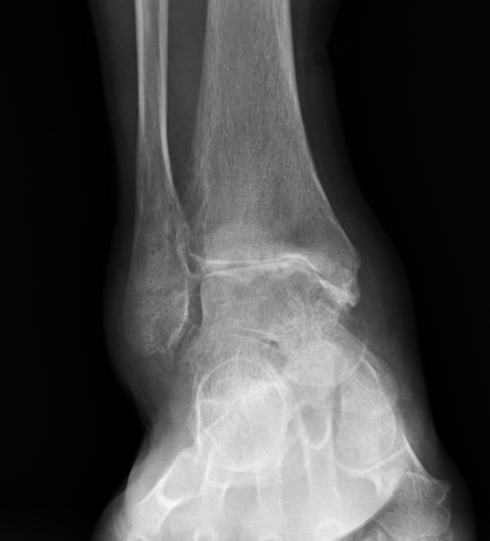

인간의 뼈와 가장 유사한 성질을 가진 금속과 마찰계수가 작은 폴리에틸렌으로 구성된 인공관절은 심하게 아프거나 딱딱해진 무릎을 새로운 관절로 교체해 통증을 없애고 관절 가동성을 확보할 수 있다. 수술이지만 무릎뿐만 아니라 발목에도. 관절염으로 인해 발목 관절이 심하게 손상되고, 통증이 너무 심해 걸을 수 없고, 약물, 물리치료 등 다른 방법으로도 해결할 수 없는 경우 인공관절 치환술을 고려할 수 있습니다. 인공관절 치환술. 과거에는 발목관절염이 심할 때 통증을 완화하기 위해 관절유합술을 시행했지만 관절유합술은 발목 관절을 구부리고 펴지 못하는 장애를 남기고 있어 큰 불편을 겪었다. 관절 교체 수술은 발목 움직임을 유지하면서 통증을 제거하는 혁신적인 대안입니다. 발은 인체에서 가장 많이 사용되는 부위로 발의 건강을 좌우한다고 합니다. 이것은 매우 중요한 부분입니다. 자주 사용하는 부품이기 때문에 쉽게 다칠 수 있지만 매우 중요한 부품이기 때문에 다치지 않도록 각별한 주의가 필요합니다. 발목이 심하게 다친 경우에는 인천모두병원에서 소개하는 인공발목관절 치환술로 치료가 가능하지만 다치지 않도록 주의하시고 수술을 피하시기 바랍니다. 발목 수술은 병원의 모든 것!부상을 당하여 어떠한 치료를 받아도 상태가 호전되지 않는다면 인천 남동구 모도병원에서 인공관절 치환술을 고려해보시기 바랍니다. 한계를 극복하기 위해 1. 최소침습수술(MIS) 기술을 이용한 개인 맞춤형 인공관절 2. 풍부한 경험을 갖춘 숙련된 의료진의 고품질 수술(정밀 절골술, 인대 균형 등) 기술 4. 수술 절개 부위가 작아(약 10cm) 회복이 빠르고 흉터가 작습니다. 발목 관절 성형술은 발목 치료의 거의 마지막 단계입니다. 모두의병원에서는 약물치료, 물리치료, 인공관절 치환술 등 비교적 간단한 치료가 가능합니다. 즉, 다양한 치료방법으로 치료가 가능하기 때문에 환자의 상태에 따라 치료를 하게 됩니다. 발목의 통증을 방치하지 마시고 인천 남동구 모두병원으로 내원하시기 바랍니다. 모두병원 인천광역시 남동구 농구애로 88